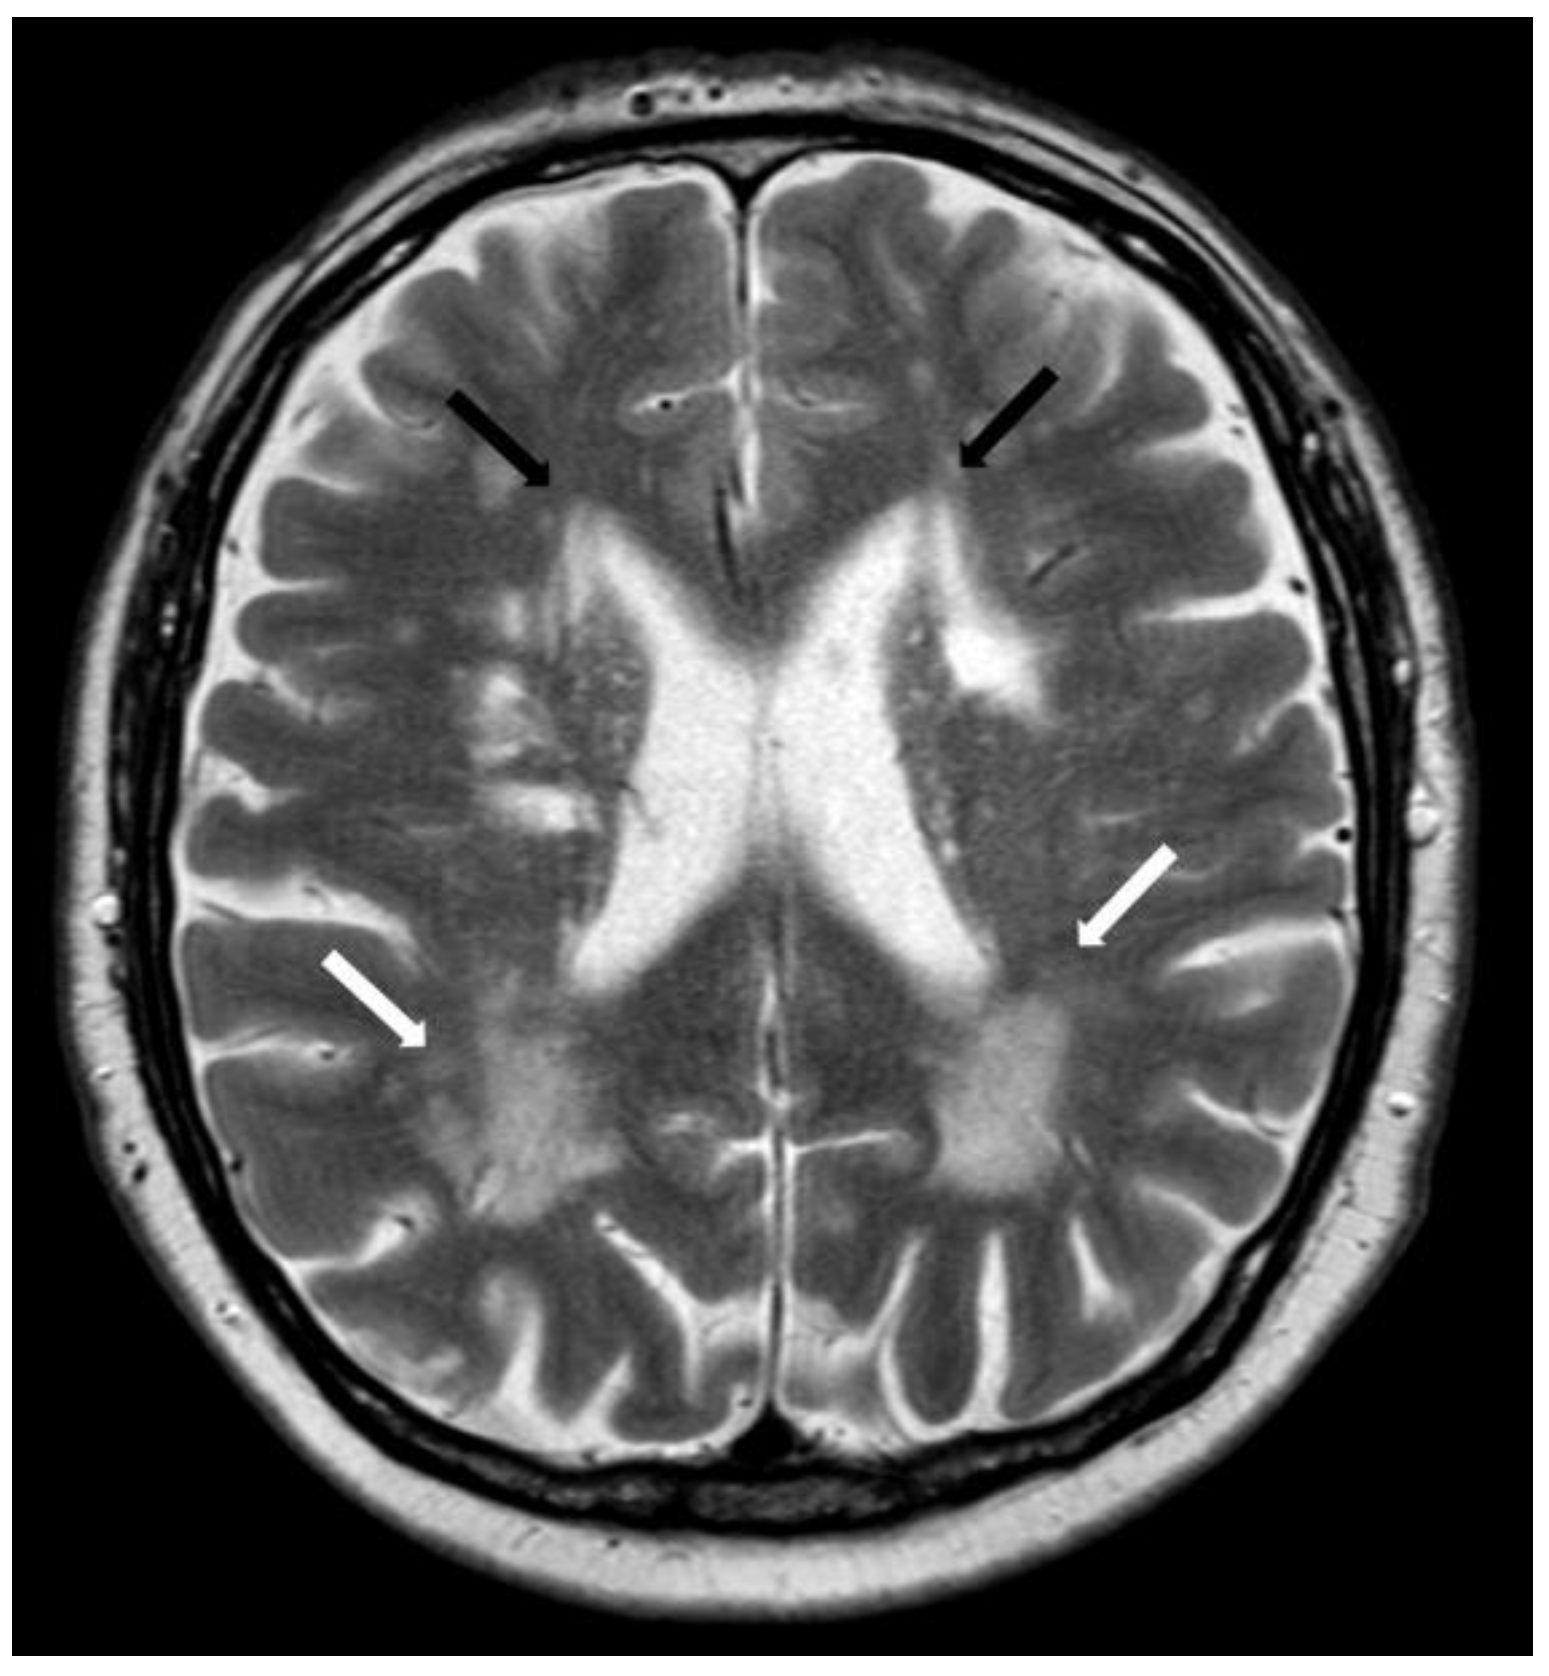

5.2.1. Enlarged Perivascular Spaces

5.2.2. Subcortical White Matter Lesions